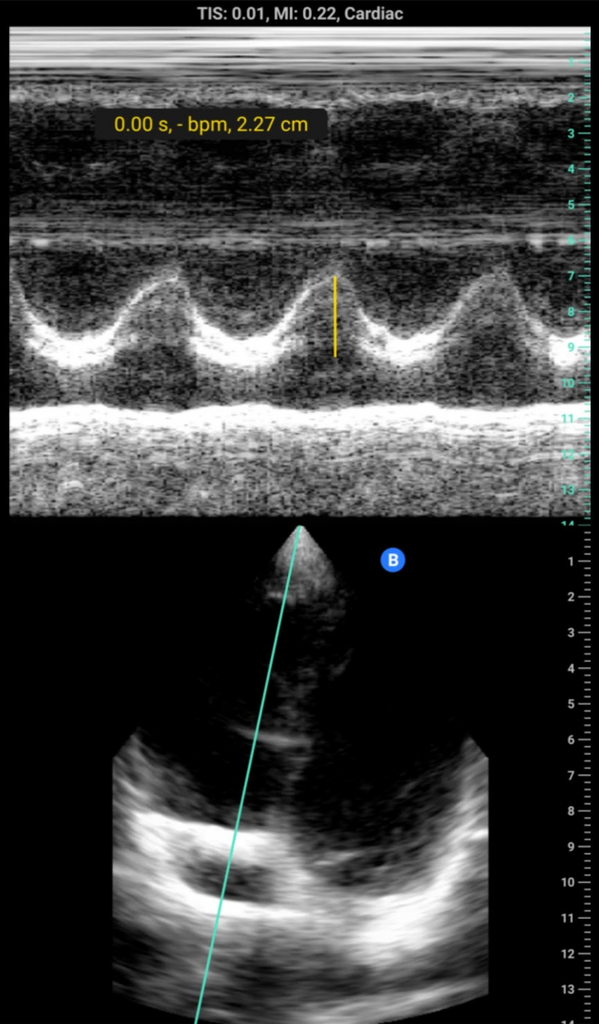

I just got my Butterfly IQ+ with lifetime membership for $3K because it's reimbursed for me. I haven't tried it much and was struggling a bit with TTE but maybe that's me since I'm somewhat inexperienced with TTE. My nerve views looked great though! I currently have a Samsung Galaxy S9 and am waiting until the new Samsung comes out so I can get a new phone with a bigger screen.

As an update, the TTE is variable. I've been getting a bit better windows on myself but still not great. Yesterday, an old lady didn't look so great after extubation and I got great PLAX and PSAX views immediately just 30s after pulling it out of my bag and plugging it in. I preordered the Samsung Galaxy S21 Ultra, so the 6.8in screen should be helpful to have.

That would be great dude, I would love it if a cardiac trained person would give an honest assessment of the TTE. I know it doesn't do PW or CW but if the image quality is adequate for regional wall motion and very rough valve morphology/motion, along with color, that might be enough for me to get one.

It does both PW and CW, actually. I haven't used then much yet though. One of my co-workers is did a cardiac fellowship and is pretty happy with the probe overall, and he doesn't even have the newest one.

Wow I’m really impressed it does CW and PW and I saw some pics above with it! Can it also trace and those kind of functions as well? So I can calculate VTI etc?